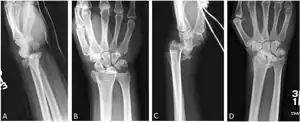

A Barton fracture is a type of wrist injury where there is a break of the front or back of the radius nearest the hand, resulting in the wrist being pushed out of place.[1] It typically occurs after falling on on top of a bent wrist.[2]

There exist two types of Barton's fracture – dorsal[3] and palmar, the latter being more common. The Barton's fracture is caused by a fall on an extended and pronated wrist increasing carpal compression force on the dorsal rim. Intra-articular component distinguishes this fracture from a Smith's or a Colles' fracture.

Treatment of this fracture is usually done by open reduction and internal fixation with a plate and screws, but occasionally the fracture can be treated conservatively.

Barton's and reverse Barton's